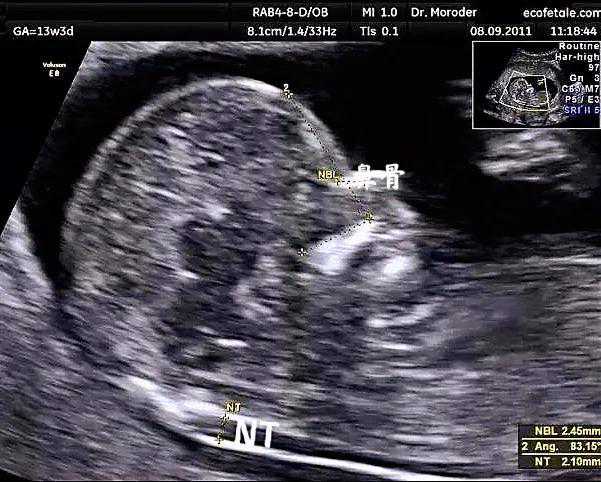

第二次超声检查在孕11到孕13周6天之间,检查主要内容:测量NT,也就是胎儿颈后透明带。通过NT数值,结合孕妈的年龄,血清学指标,综合判断胎儿唐氏综合征的风险。除了测量NT,在这次超声时,可以大致进行胎儿一些结构的观察,如有无头颅,有无缺少一侧肢体,有无大的脐膨出等,可以更早期的排除一些严重影响胎儿的结构畸形如:无脑儿等。但是更加详细的结构观察还是要到中孕期的系统筛查,也就是俗称的大排畸。

值得大家期待的是,在我们一妇婴检查超声,您的报告上都会有一张图2所示的宝宝的照片哦。

图2图中箭头指的就是宝宝的NT